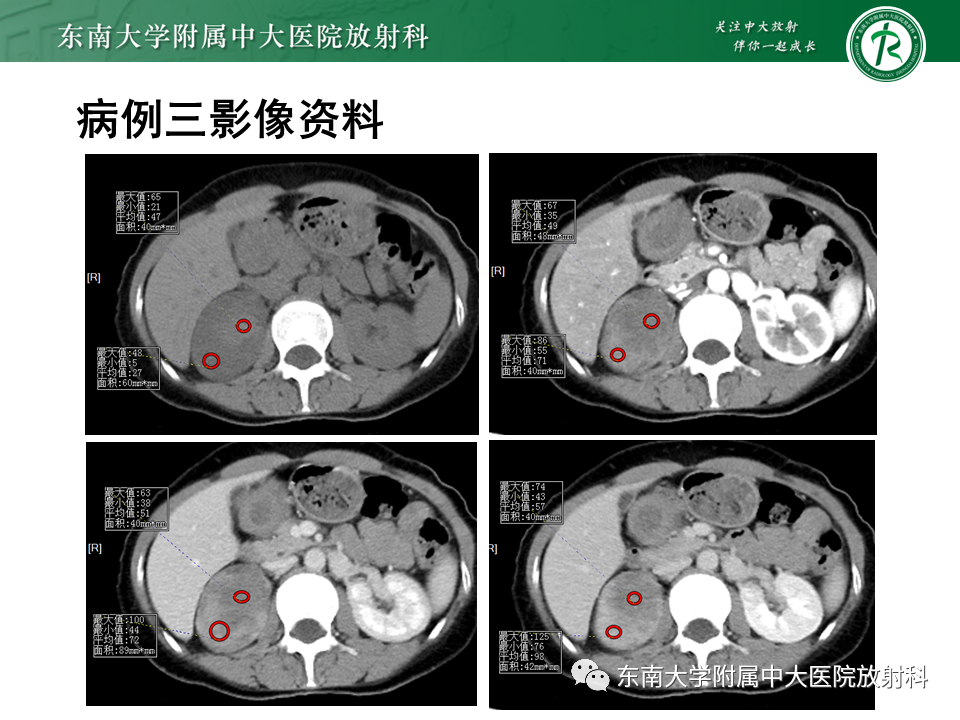

病例1:肾上腺血管瘤伴破裂出血;病例2:肾上腺脓肿;病例3:黏液性肾上腺皮脂腺瘤